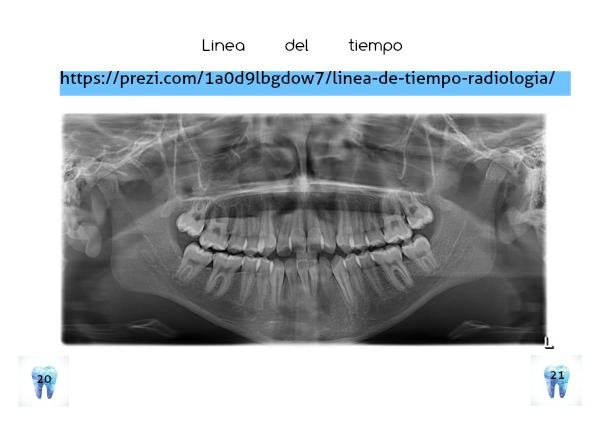

RADIOLOGIA LGRG no° 1 | Page 20